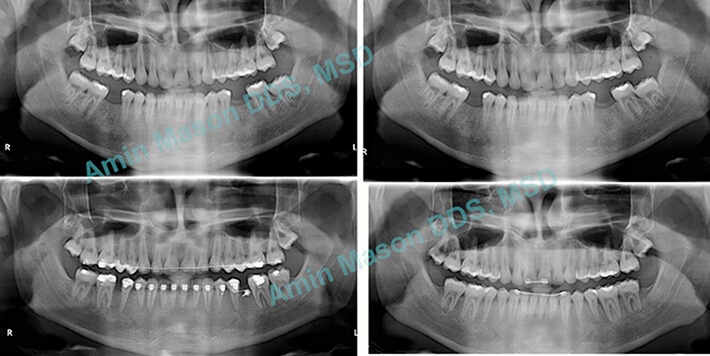

Molar Protraction Case

Adult patient with missing mandibular first molars. TADS were used to protract (pull forward) the 2nd and 3rd molars (wisdom teeth). Patient was saved from getting implants for the missing teeth.